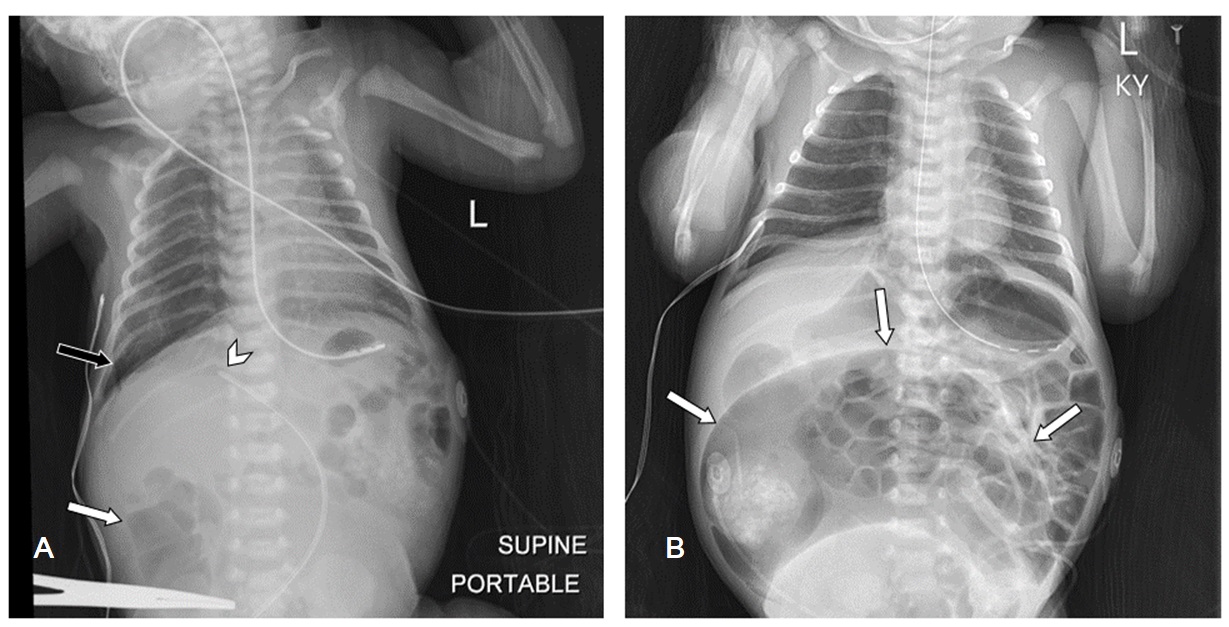

Chest and abdomen radiographs approximately 14 hours apart demonstrating rapid progression of bowel dilation. A) Day of life 0 radiograph shows a nonobstructive bowel gas pattern with mild distention of the right colon (white arrow). Note the malpositioned umbilical venous catheter-directed towards the right portal vein (arrowhead) and small right pneumothorax (black arrow). B) Day of life 1 radiograph shows massive gaseous dilation of the congenital sigmoid pouch colon (arrows).